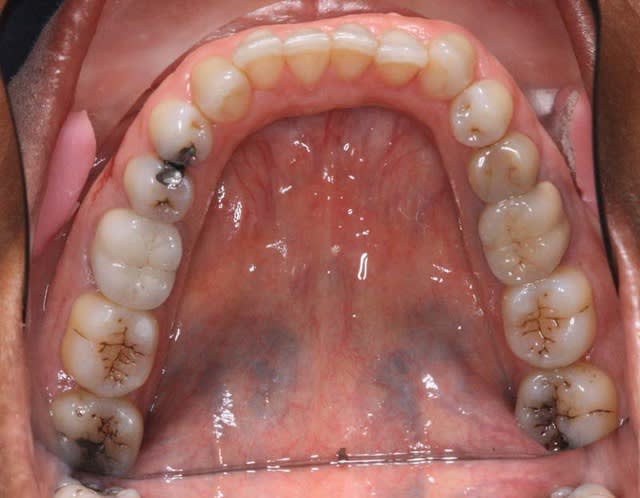

pas de Pbs. psy, voici les Rx.

douleurs coté G.

@+ Bjc.

il n'y a rien qui vous choque dans la forme d'arcade Md. ?

> il n'y a rien qui vous choque dans la forme d'arcade Md. ?

qu est ce que tu veux dire ? sa dissymétrie ? le U un peu déformé qu'elle exprime ?

Si ce n'est pas la différence entre l’arcade en U et l’arcade plus harmonieuse en haut et bien je donne ma langue au chat ou l'absence de symétrie.....

"""Des acracdes imparfaites comme ça ne me suffisent pas à poser un diag."""

et l'exostose complète palatine au Max. Sup. ?